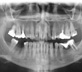

Clique nas imagens p/ampliar

Radiografia Panorâmica

A radiografia panorâmica, como o próprio nome diz, oferece ao cirurgião dentista uma visão ampla das condições dos dentes e osso alveolar, do osso da mandíbula e da maxila, bem como dos seios maxilares. Considerando que 2/3 dos dentes encontram-se imersos no osso alveolar da maxila e mandíbula a avaliação dos mesmos por meio de radiografias é imprescindível ao cirurgião dentista que busca um completo panorama da saúde bucal de seus pacientes.

A SCAN utiliza o Cranex D para obtenção de imagens panorâmicas. Com tecnologia digital de aquisição direta, o Cranex D oferece máximo conforto e muita rapidez na execução dos exames.